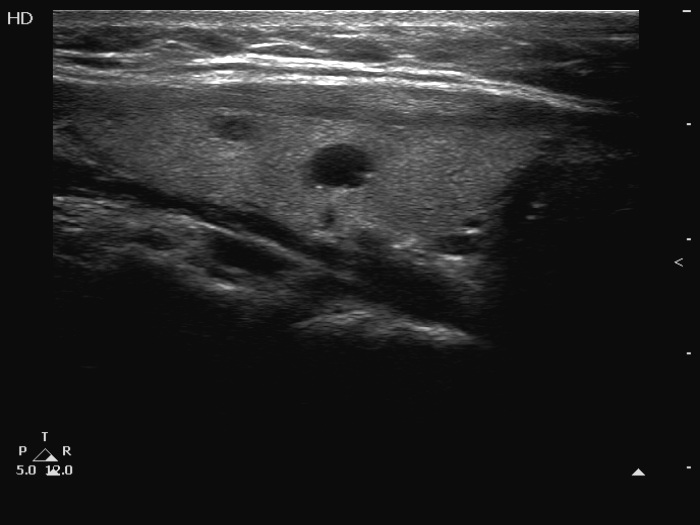

Before surgery (ultrasonographic picture 2)

Right lobe, longitudinal view.